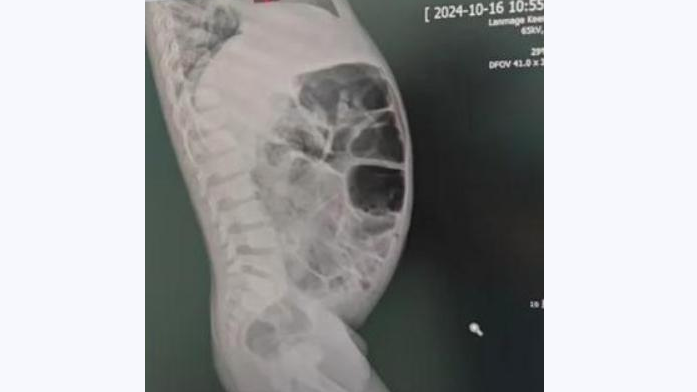

從報道顯示的X光片看見,體積不細的玻璃瓶在肛門內較高位置,醫生最後成功取出它,連帶一個安全套。報道稱,那男子將一個容量500毫升的玻璃瓶塞進肛門,並將其推進腸道,最後因無法取出而求醫。俄羅斯下諾夫哥羅德一間醫院公開有關個案,稱醫生非道德警察,不會評論病人非傳統的性傾向,呼籲民眾若遇相同情況,須尋求醫療協助。